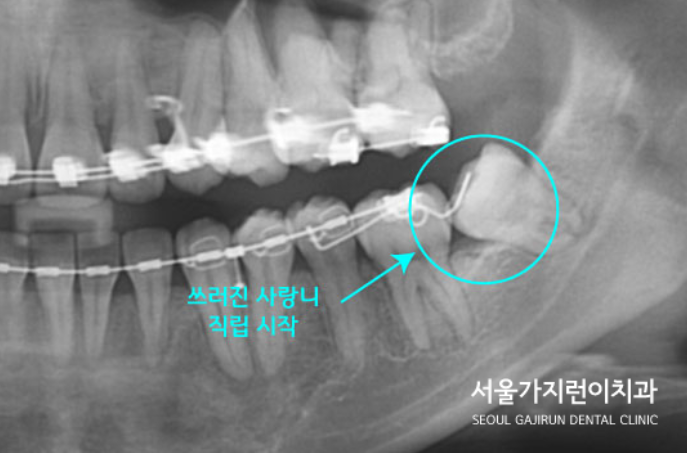

본원에서는 MBC 스프링 교정방식으로 사랑니를 서서히 세웠는데요.

7개월 정도 지났을 때 직립된 모습을 확인할 수 있었습니다.